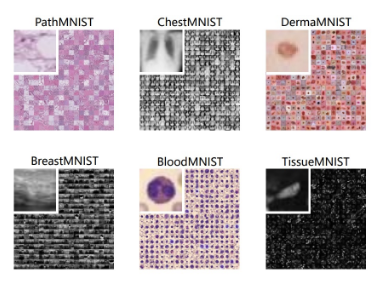

MedMNIST医学图像分割评估

下载链接:http://ew0b7.avtk.cn/db

MedMNIST,这是 10 个预处理的医学开放数据集的集合。MedMNIST 经过标准化处理,可在轻量级 28x28 图像上执行分类任务,无需背景知识。它涵盖了医学图像分析中的主要数据模式,在数据规模(从 100 到 100,000)和任务(二元/多类、序数回归和多标签)上具有多样性。MedMNIST 可用于教育目的、快速原型设计、多模式机器学习或医学图像分析中的 AutoML。此外,MedMNIST Classification Decathlon 旨在对所有 10 个数据集上的 AutoML 算法进行基准测试